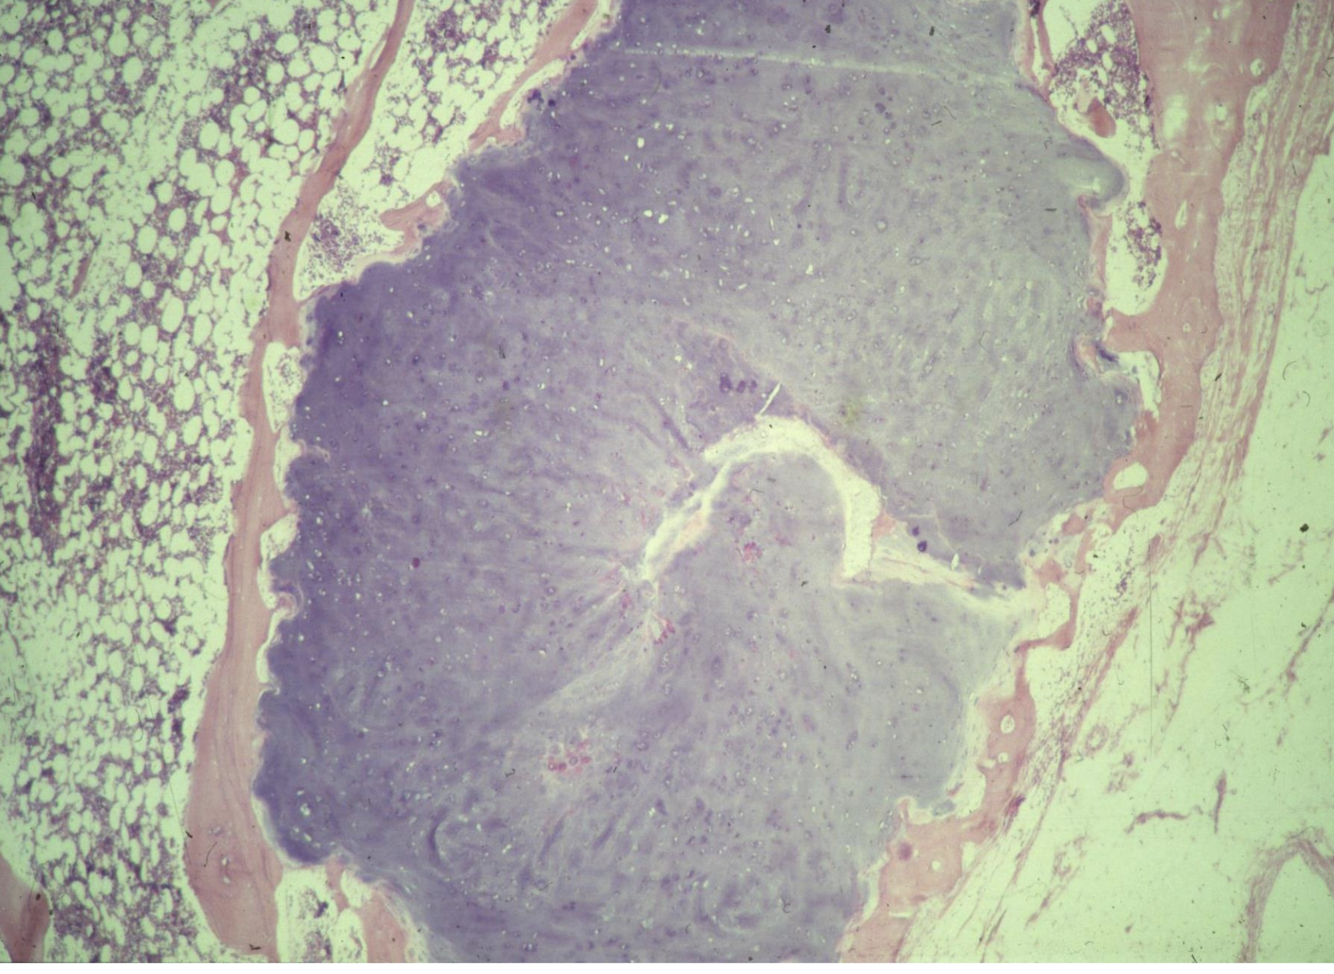

Bone histology of a lesions shows

Cartilage capped “mushroom” bony outgrowth - what is the diangosis?

A

Osteochondroma

Show’s normal bone covered by cartilage